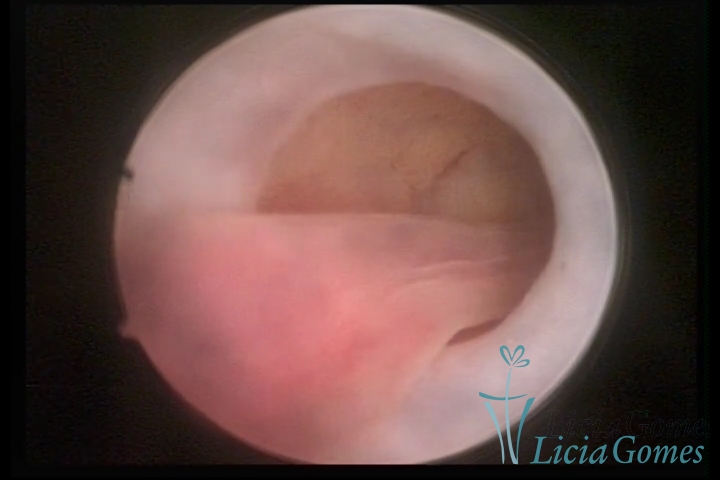

ENDOCERVICAL POLYPS

Benign tumors resulting from the reactive focal proliferation to inflammatory processes or hyperestrogenism situations, which may be sessile (with a large implantation) or stalked.